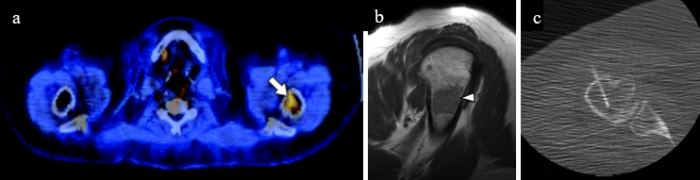

Fig. 4A —62-year-old woman with lymphoma and colon cancer who presented for oncology surveillance. A, Axial image from FDG PET/CT shows increased FDG avidity (arrow) in proximal humerus. B, Sagittal T1-weighted MR image shows overall hypointensity of lesion (arrowhead), though mild hyperintensity relative to skeletal muscle, suggestive of red marrow. Lesion was occult on CT at time of biopsy. C, Axial CT image from core needle biopsy shows biopsy needle in lesion, which was targeted according to anatomic landmarks with respect to prior imaging. Pathologic report described mildly hypercellular marrow with maturing trilineage hematopoiesis but no malignancy.